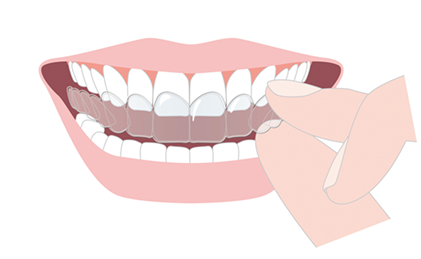

歯ぎしり治療にはナイトガード(就寝時に装着するマウスピース)を使用します。

したがって睡眠障害や睡眠習慣を改善することが必要ですが、その間もナイトガードと呼ばれる「マウスピースによるスプリント療法」で歯ぎしり力から歯や歯ぐき、顎関節を守るための対応をします。

マウスピースを就寝時に装着することで、

歯・顎関節・首・肩などにかかる負担を減らすことができます。

現状では、歯ぎしり食いしばりによる問題から守り、お口の状態を長く良い状態に保つための「管理」としてナイトガードを使用していくことが最善です。

したがってその間もナイトガードを使用し、歯や顎を守る必要があります。